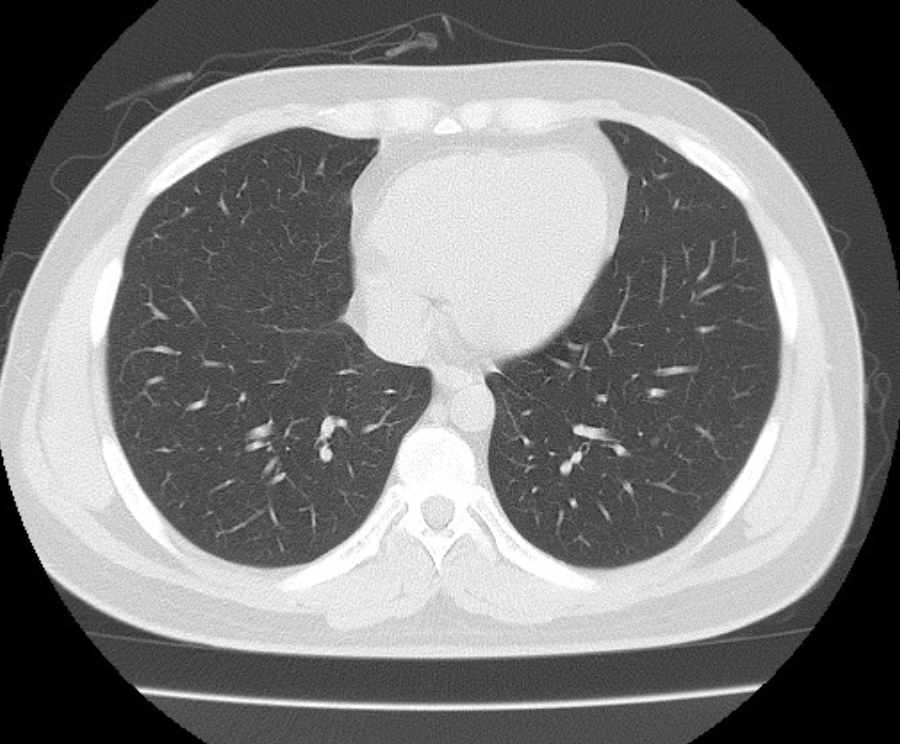

폐ct사진 받았는데 엄청 많더라구요.. 우중엽(40#)에 부분고형결절(6mm, 고형 2mm)결절이 있다고 소견을 받았는데 아래 ct사진 상 위험한 결절로 보이는지 판독좀 부탁드리겠습니다 ㅜㅜ. 다른 사진들 더 많지만 앞뒤 전후로 몇장씩만 가져왔어요..

• 3번 째 사진

그러네요 결절이 눈에 보이네요

환자분이 어느 군에 포함이 되는지 확인을 해보시면 어느 정도 안심을 할 수 있으리라 생각이 됩니다

해당 소견을 바탕으로 호흡기내과 진료를 받아보세요